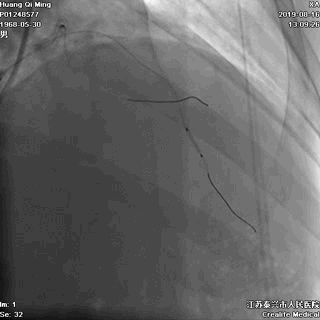

2.0*25 药物洗脱球囊,8atm*60秒释放药物

2.5*25 药物洗脱球囊,8atm*60秒释放药物

术后即刻效果满意